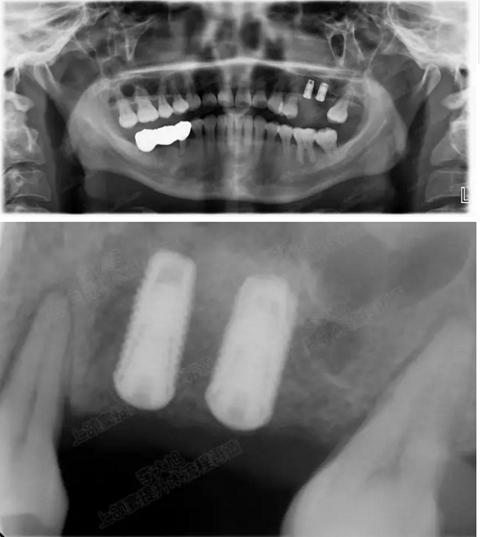

病例一

上頜竇多分隔3mm

05.png

提升8mm

06.png

07.png

修復(fù)時(shí)根尖片

08.png

09.png

口內(nèi)照片

001.png

修復(fù)后一年

002.png